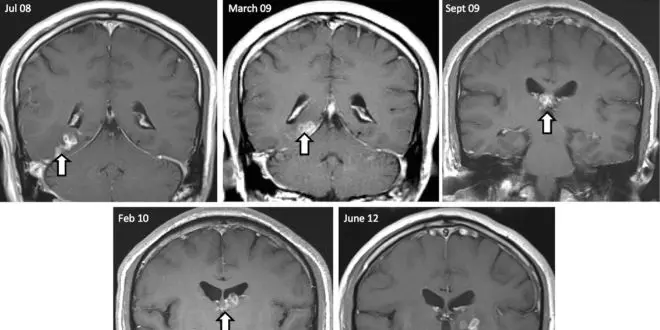

Un homme de 50 ans d'origine chinoise, résidant aux Royaume-Uni depuis 20 ans, souffrait depuis de longs mois de maux de tête, de troubles de la mémoire et de l'odorat, ainsi que de crises d'épilepsie toniques-cloniques (raideurs musculaires suivies de spasmes). A la fin des années 2000, il fut admis à des fins d'examens dans un hôpital de la région de Cambridge. Là, une IRM cérébrale révéla la présence d'une sorte d'œdème au niveau du lobe temporal droit.

A l'occasion d'une nouvelle IRM, les médecins furent surpris de voir que "l'œdème" s'était déplacé dans le cerveau du malade. Quatre années durant, les imageries se suivirent sans se ressembler : au terme de cette période l'anomalie s'était déplacée de plus de 5 centimètres dans le cerveau, sans pour autant grossir.

Une biopsie révéla alors la composition "l'œdème" : une larve vivante de Spirometra erinaceieuropaei, un ver plat proche du ténia.

Mesurant 10 centimètres de long elle avait élu domicile dans la boîte cranienne du patient depuis de longues années.